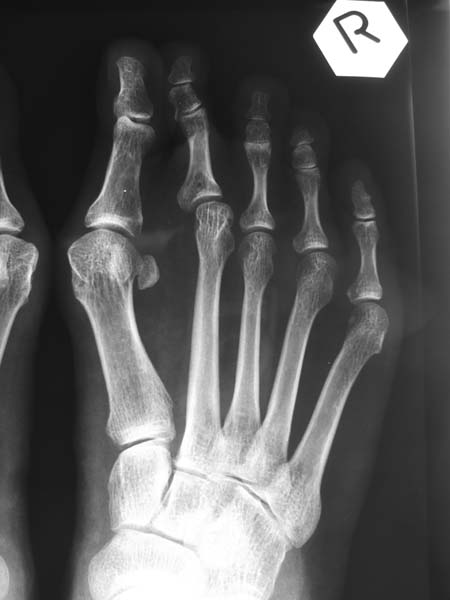

This is a lady with a painful bunion of her right foot and the 2nd toe has become over-riding.

This is the x-ray finding: